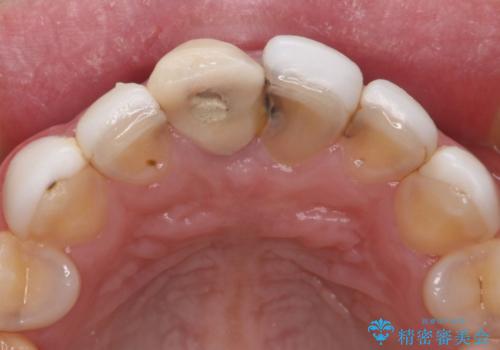

- 他院で治療した前歯の色が気になるということで来院された患者様です。前歯に色の差があり、レントゲンから内部にう蝕も見られたため、審美性に優れ、う蝕になりにくいオールセラミッククラウンで治療いたしました。